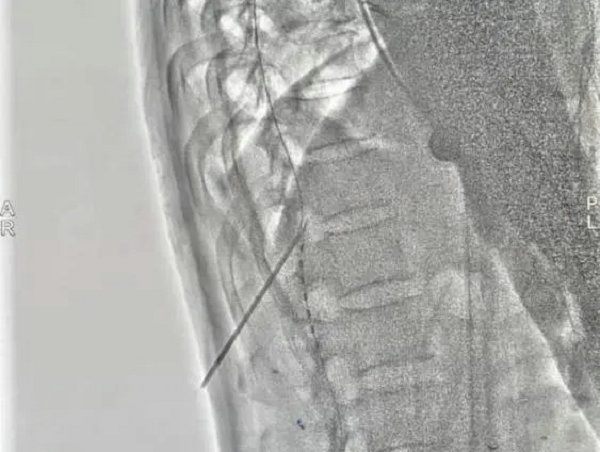

4月27日在医院复合手术室,由寿记新主任医师、管海博主治医师共同完成颈段及腰段短时程脊髓电极植入术,为患者尽早拔除气管套管、完全清醒、站起来、能走路、回归生活奠定了良好基础。

1、创伤更小:短时程脊髓电刺激器置入术,创口仅为皮肤穿刺点,约5毫米。术中基本不出血或者出血量极少;永久性脊髓电刺激需全麻下在颈后部正中做长约8cm手术切口。

4、手术时间明显缩短:短时程脊髓电刺激手术操作时间约30—60分钟,永久性脊髓电刺激手术操作时间约2—3小时。